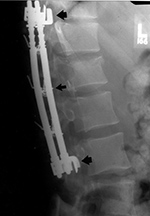

| Steffee pedicle plates and screws |

| Frontal and lateral views in two different patients show bilateral Steffee plates and screws in the lumbar spine with two side by side Brantigan intervertebral cages (arrows) at L2-3. |